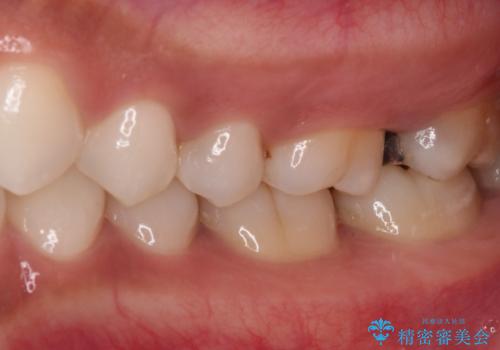

- 奥歯にフロスが引っかかるようになり、虫歯ではないかとのことで来院された患者様です。

レントゲン写真より、左右奥歯にむし歯があることが分かりました。

奥で目立たないことから、虫歯の再発リスクが最も低く、咬合力による歯への負担も少ないゴールドインレー(PGAインレー、白金加金インレー)にて修復治療をすることとしました。